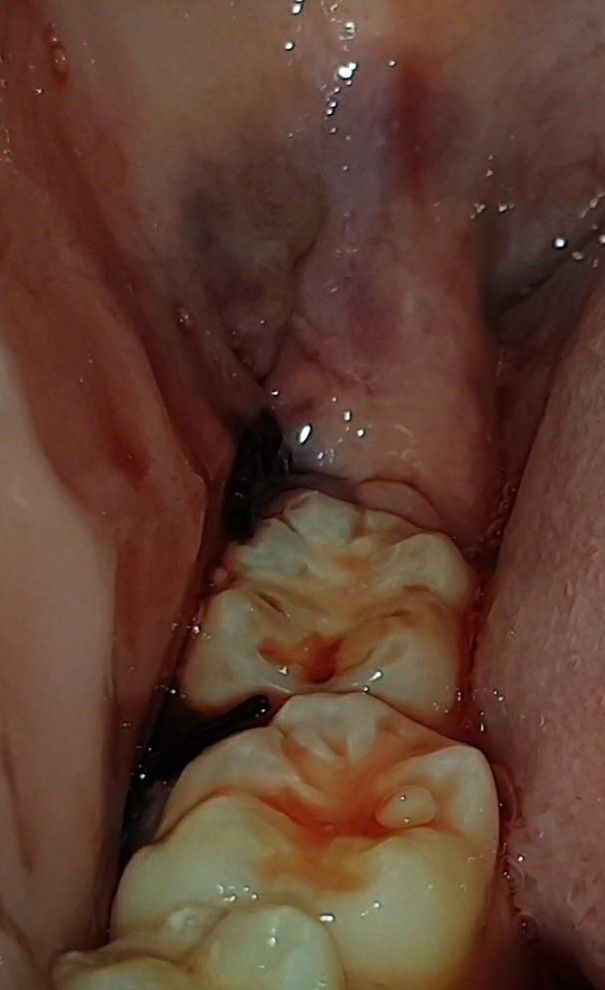

매복 사랑니 발치 후 실밥이 풀린 것 같아요

그저께 발치하고 어제 오후에 실밥이 풀렸는지 피가 조금씩 스며 나왔어요 자고 일어나니까 오늘은 저런 상태인데 양치했을 때만 피가 조금 나오다 말아요 어금니에 걸쳐져 있는게 실밥인데 치과는 담주 실밥 푸는 날에 가도 되나요?

• 2번 째 사진

실밥이 풀리더라도 문제가 생기는 경우는 거의 없습니다. 지혈이 잘되었다면 내원날짜에 가시면 됩니다.

피가 많이 나시는거 같은데 최대한 사랑니 발치한곳에 자극을 주지 않는게 좋습니다. 실밥은 약속된 시간에 가셔서 푸셔도 될것같습니다.

실밥이 좀 길게 남겨지긴 했으나

정상이십니다.

걱정하지 않으셔도 됩니다.